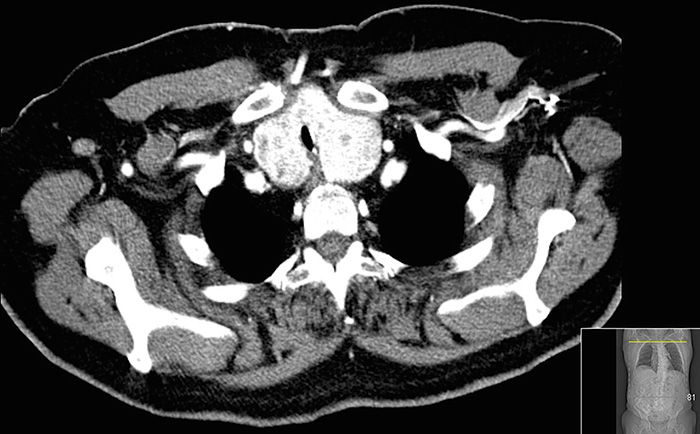

Fall 3. Det avslutande fallet var en 74-årig man med hypertoni och typ 2-diabetes. I samband med utredning av nyupptäckt rektalcancer hade patienten genomgått undersökning med datortomografi av torax och buk med intravenöst kontrastmedel (Omnipaque 300 mg/ml; 120 ml) 2 månader tidigare. Som bifynd på röntgen såg man en stor intratorakal struma med trakeaförträngning inom ett 4 cm långt parti med minsta lumen ca 5 mm (Figur 1). Utredning med spirometri bekräftade misstanken om ett högt andningshinder.

Figur 1. Datortomografiundersökning av torax och buk med jod­kontrastmedel visar intratorakal struma och påverkat trakealumen (fall  3).